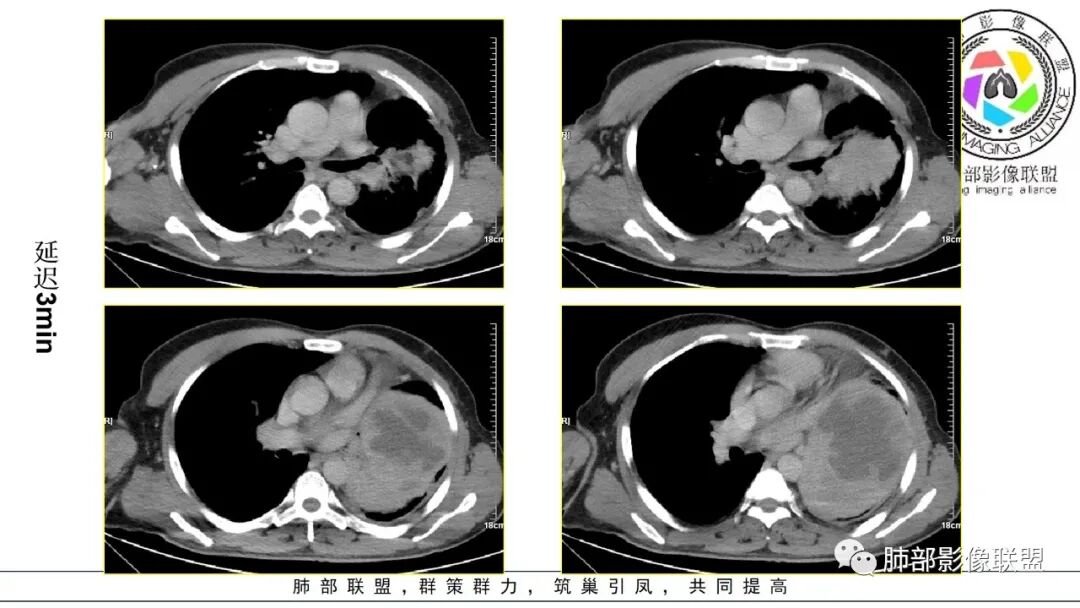

男,50岁,双下肢水肿10余天,发热3天。NSE、细胞角蛋白19片段增高。胸部CT:肺气肿背景,左下叶巨大肿块,边缘膨隆明显,与周围界限清楚,累及左肺门、左上叶,上叶支气管受压狭窄,下叶支气管截断,不均匀强化,湖泊样坏死,肿块边缘粗大点状钙化,肿块内血管影迂曲、模糊,蛇纹?考虑恶性,鳞癌?肉瘤样Ca?鉴别SFT。

2.左肺巨大块影,上部边界较清楚,占据胸腔大部,对于左肺,“占据”及“推移”兼而有之,左肺上叶支气管推移狭窄,下叶支气管截断。下肺动脉穿行!

3.病灶密度不均,轻度强化,坏死或液化范围甚大,边界可分辨,部分“壁”可见钙化。

4.病灶紧贴胸壁,胸壁未见栽赃侵入。

5.纵隔左移,左肺门变形。左肺门及纵隔未见明显增大淋巴结。